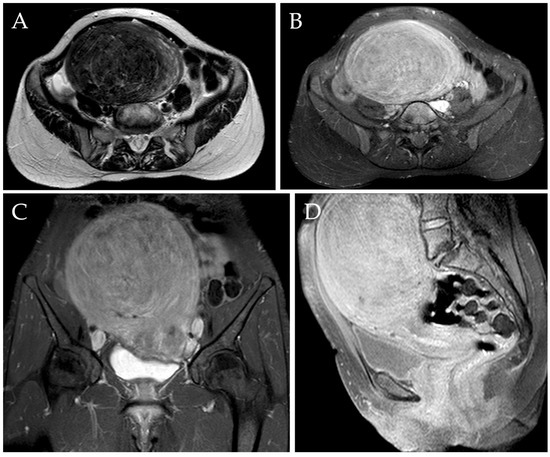

Figure 4.

Post-procedural MRI of the same patient. Axial T2-w image (A) demonstrated a reduction of the diameter of the voluminous myoma after UAE, which now measures approximately 90 mm (i.e., a diameter reduction of 35.7%). Axial, sagittal, and coronal post-contrast T1-w images with fat saturation (B–D) confirmed the diameter reduction and revealed the presence of a wide intra-tumoral necrotic area (white asterix).